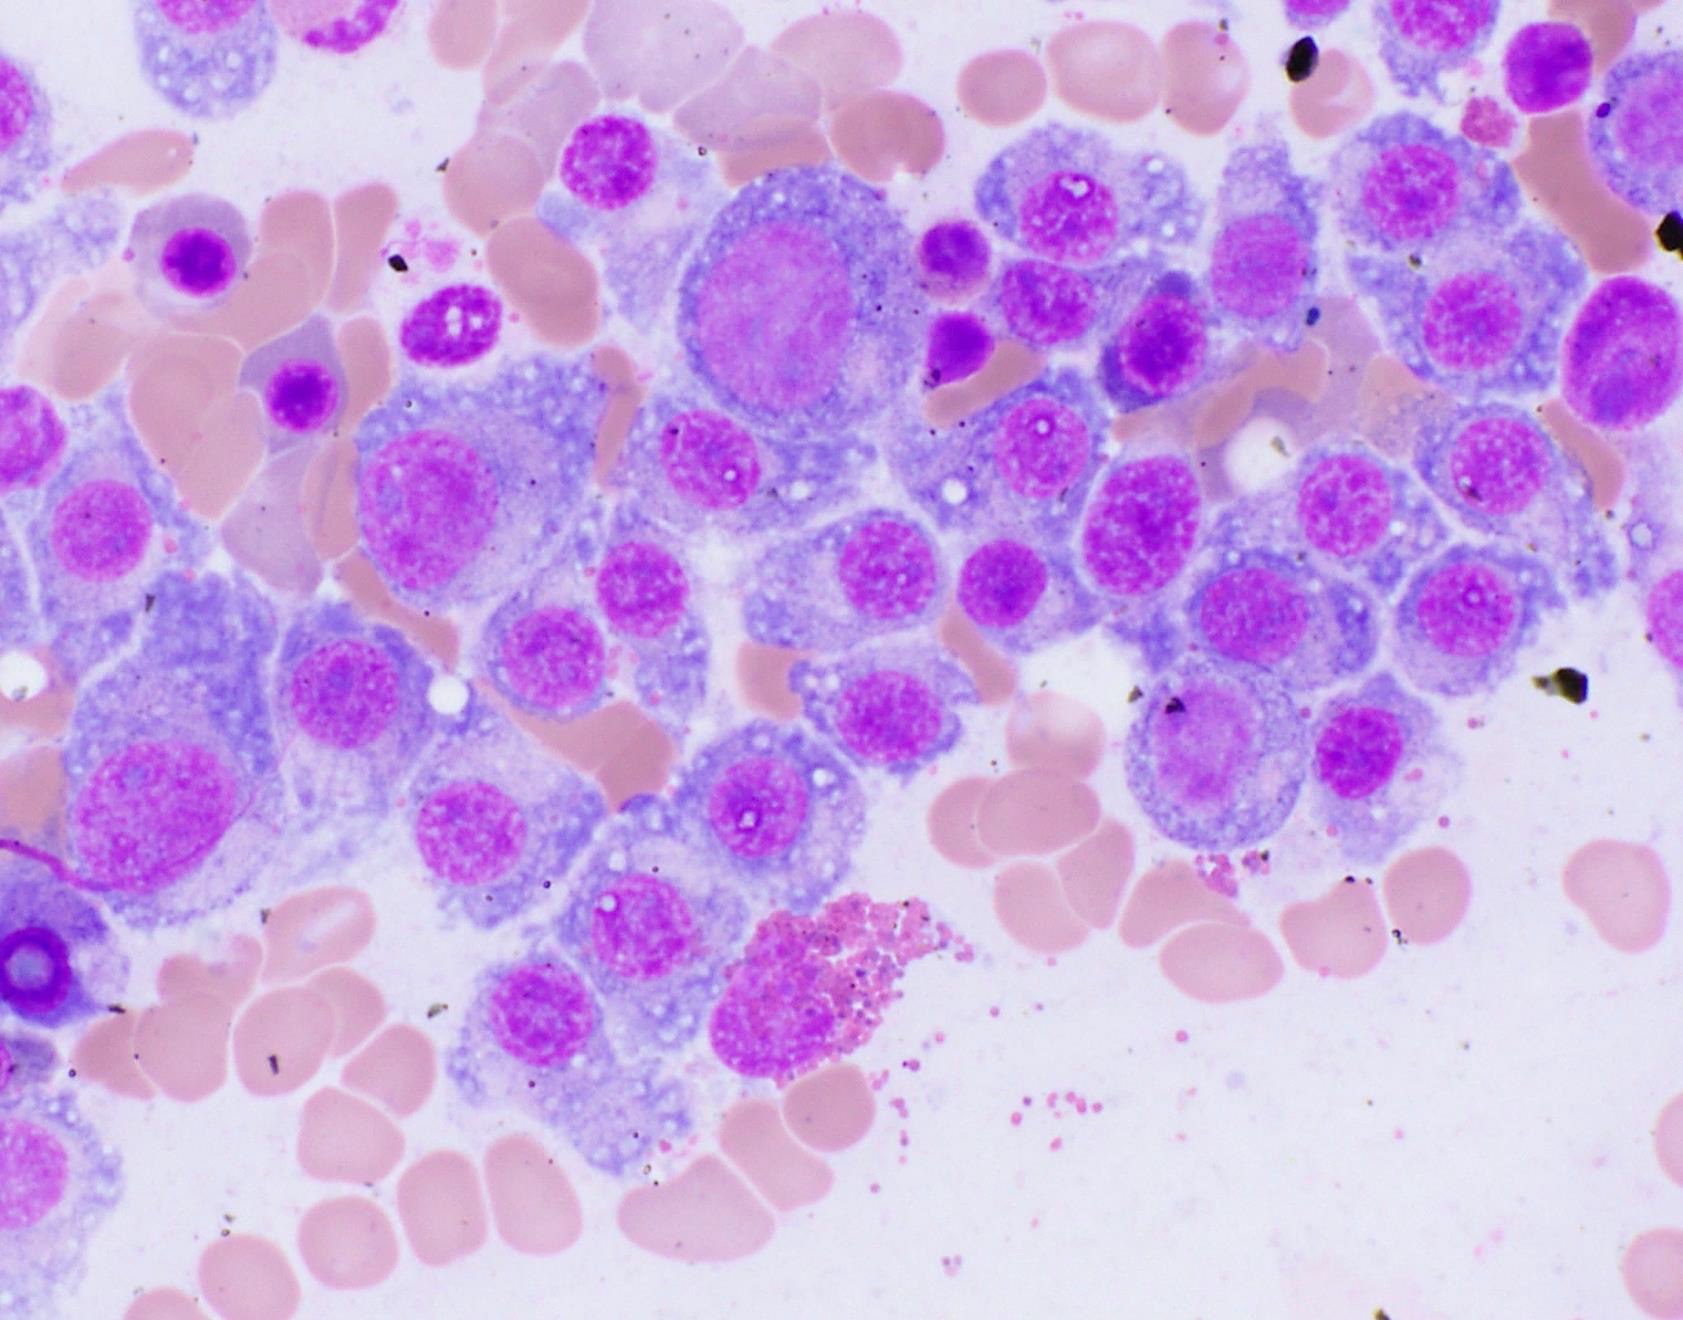

Cytology description

- Cytology can assess plasma cell morphology (e.g., mature, immature, plasmablastic) but number of plasma cells present may vary substantially from the core biopsy

- Mature plasma cells: oval with abundant basophilic cytoplasm, perinuclear hof, round eccentric nuclei, clock face chromatin and indiscernible nucleoli

- Immature plasma cells: higher nuclear to cytoplasmic ratio, more abundant cytoplasm and hof region compared to plasmablastic, more dispersed chromatin, often prominent nucleoli

- Plasmablastic: less abundant cytoplasm with little or no hof region, fine reticular chromatin, large nucleus (> 10 microns) or large nucleolus (> 2 microns) (Blood 1998;91:2501)

- Pleomorphic: multinucleated, polylobated

- Rare cases may have small, lymphoid appearing plasma cells or plasma cells with marked nuclear lobation

- Immature or pleomorphic features are rare in reactive plasma cell proliferations

- Morphologic features:

- Mott cells / morula cells: multiple grape-like cytoplasmic inclusions comprised of crystalized immunoglobulin

- Russell bodies: hyaline intracytoplasmic inclusions

- Flame cells: vermillion staining glycogen rich IgA in cytoplasmic projections (American Society of Hematology: Flame Cells in Multiple Myeloma [Accessed 26 May 2022])

- Pseudo-Gaucher cells / thesaurocytes: overstuffed fibrils (J Clin Pathol 1976;29:916)

- Cytoplasmic crystals: occasional in myeloma, common in adult Fanconi syndrome (Am J Clin Pathol 1983;80:224)

- Dutcher body: pale staining immunoglobulin filled cytoplasm invaginating into the nucleus and appearing as an intranuclear inclusion, single and usually large, more common in IgA myeloma